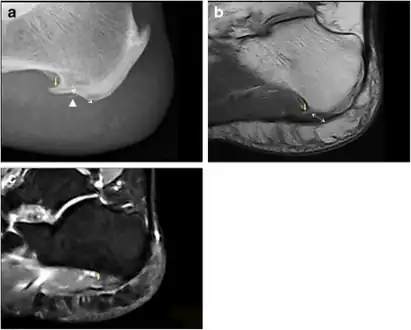

a) Plantar calcaneal spur at the origin of intrinsic muscles of the foot b) MRI confirms the presence of a calcaneal spur c) bone marrow oedema in the calcaneal spur

Inferior calcaneal spur